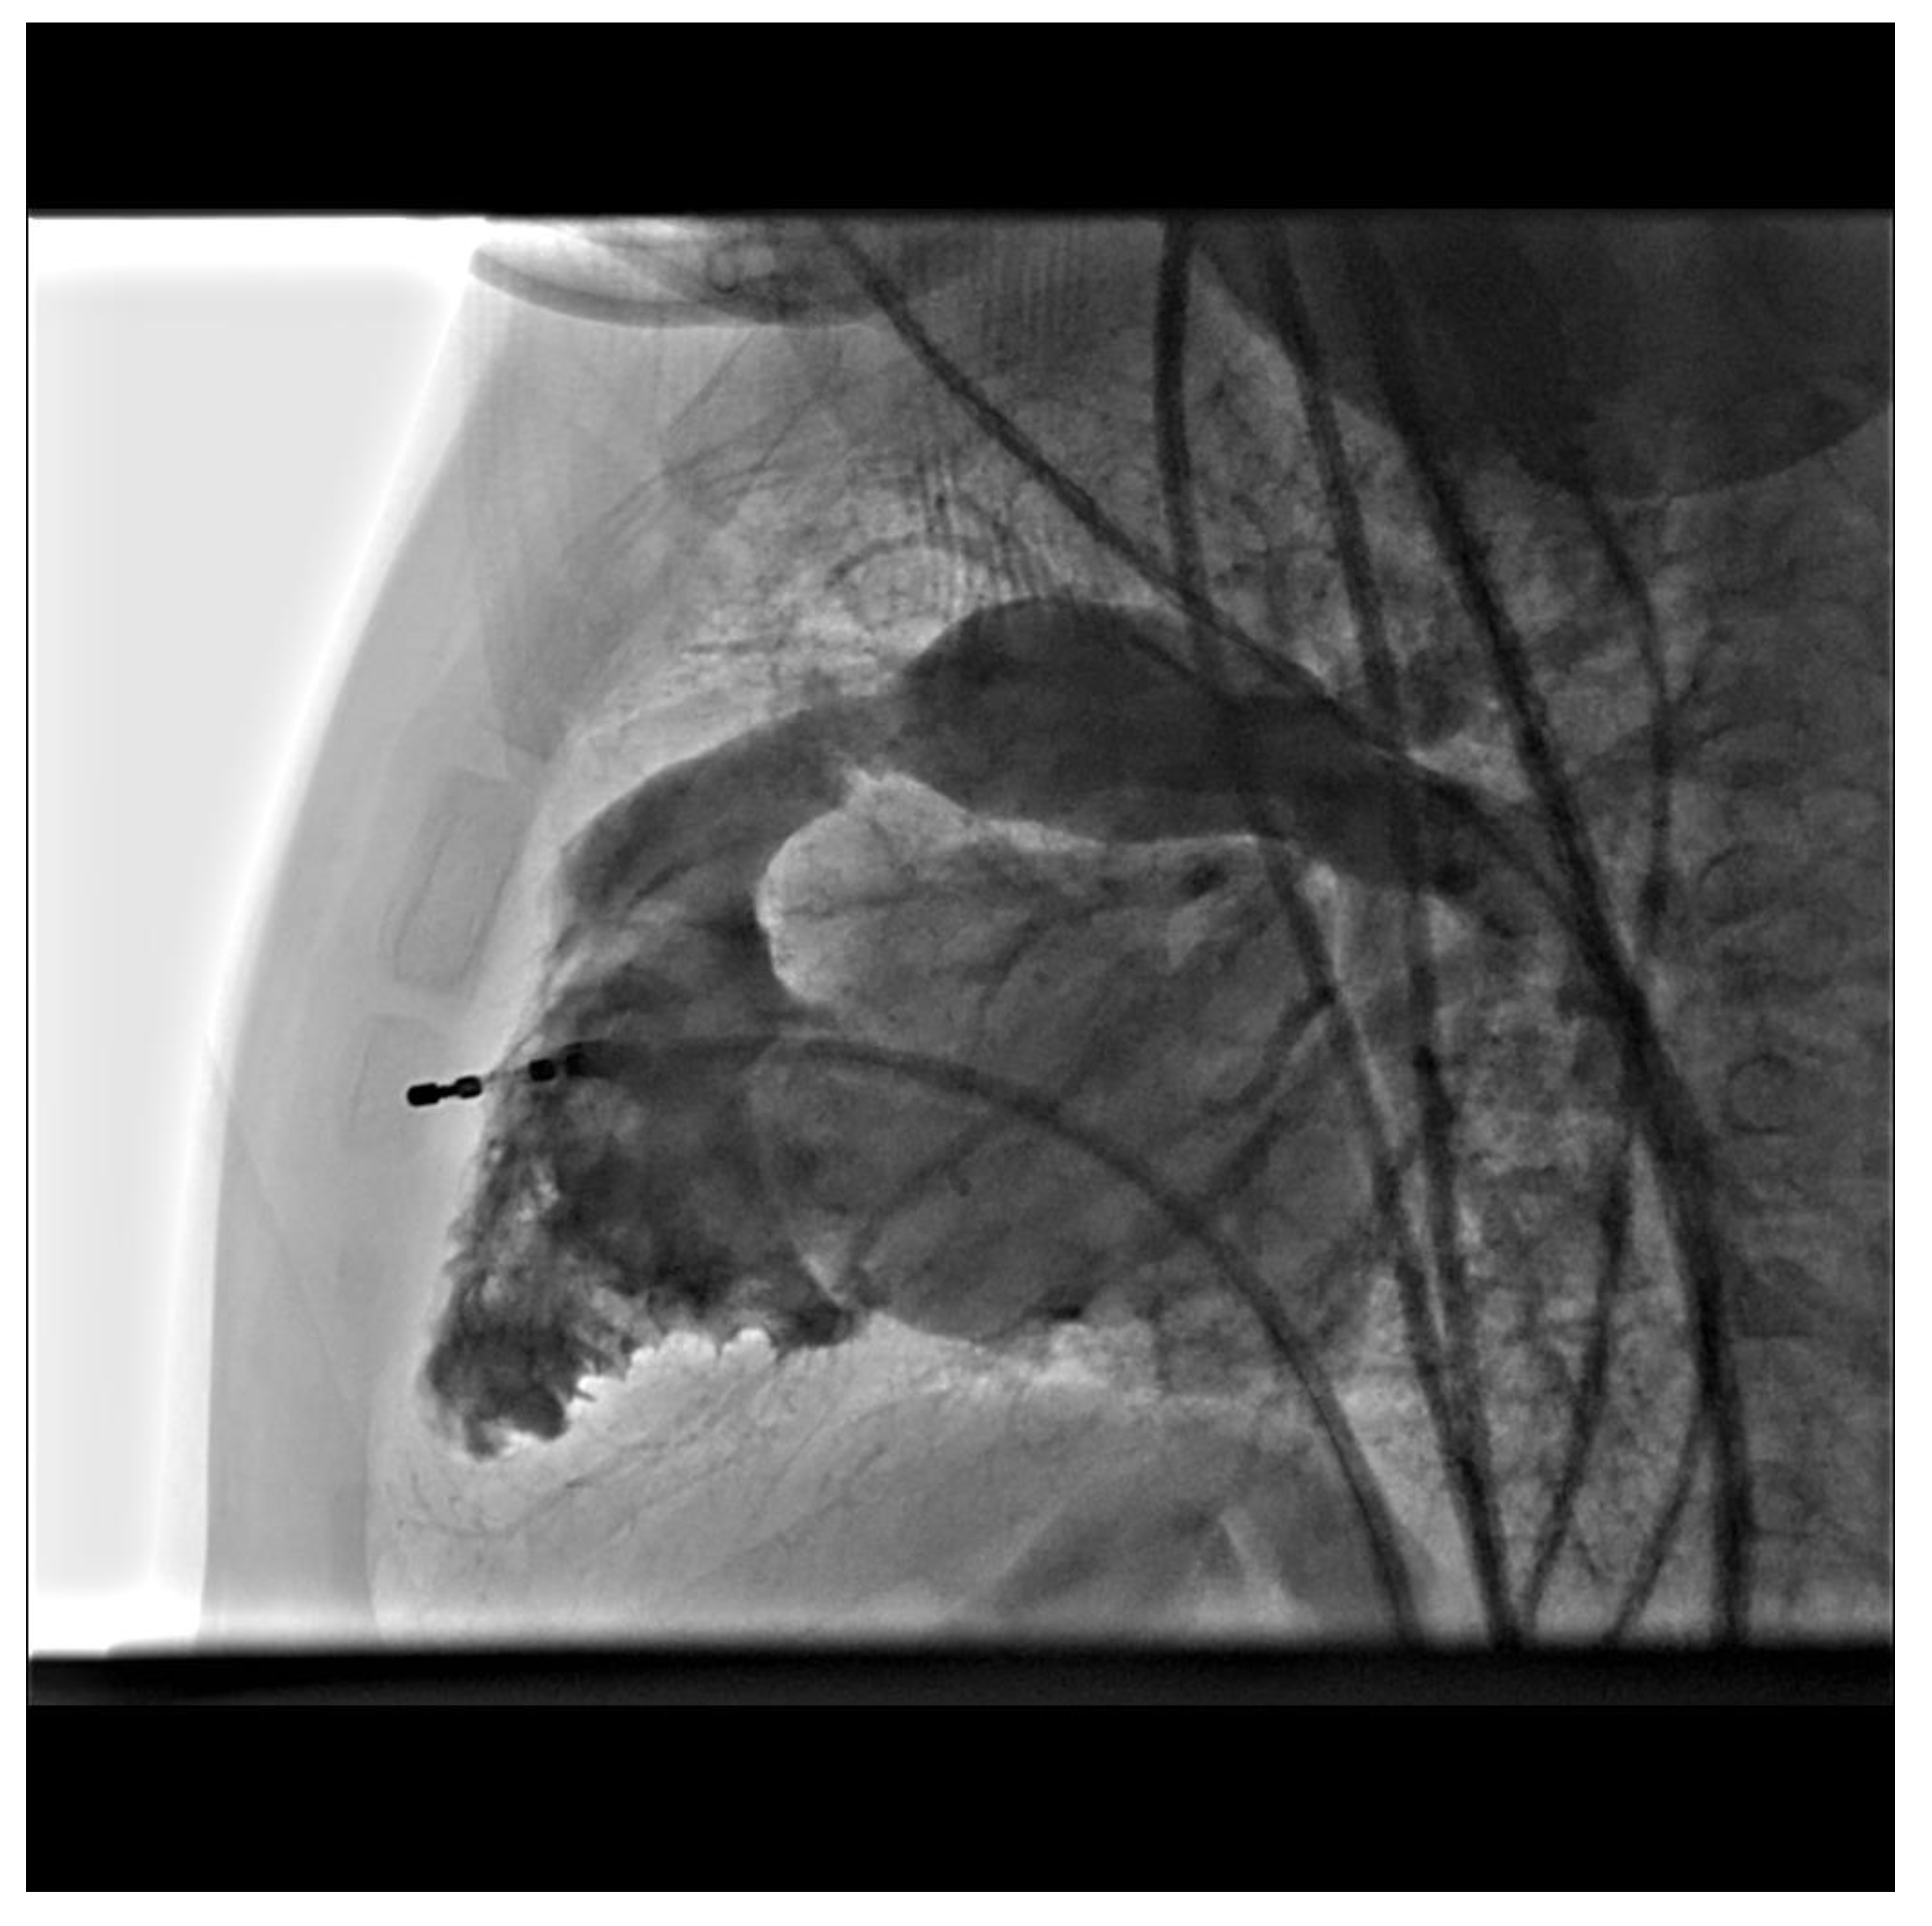

Figure 2. Lateral imaging of RVOTO taken from 3D angiography.